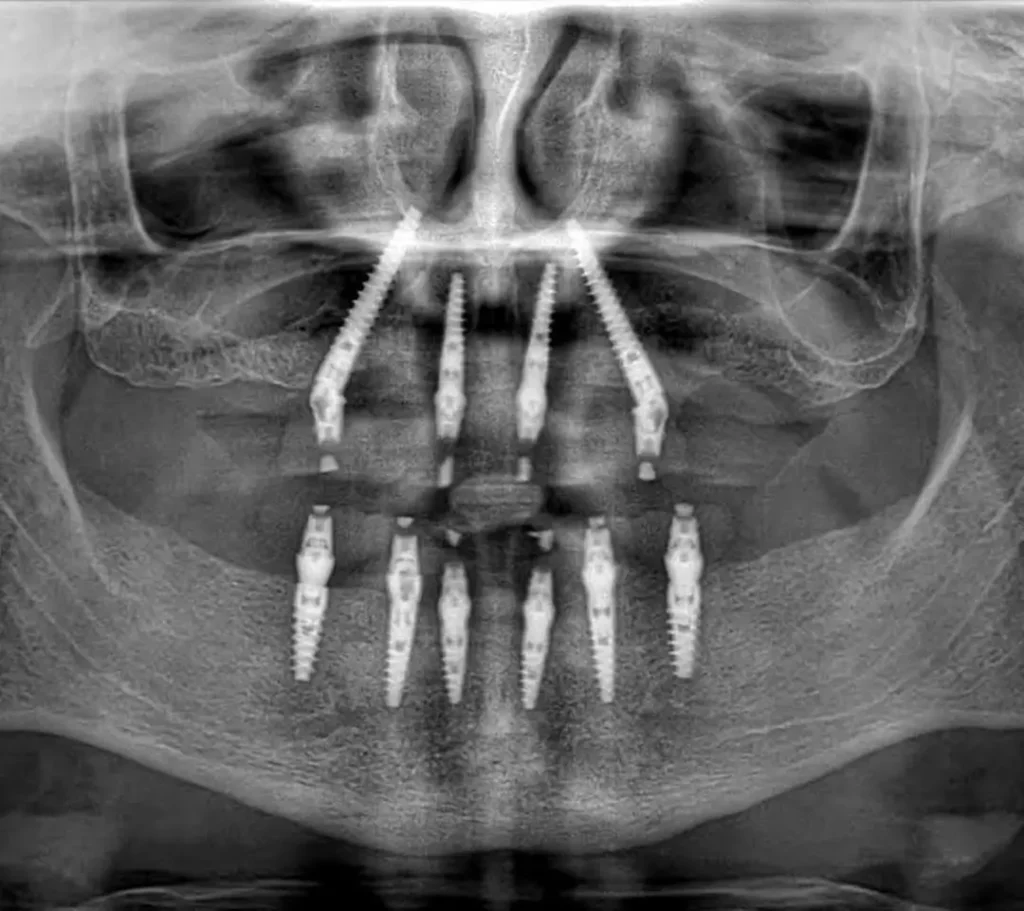

Транссинусовите зъбни импланти представляват промяна на парадигмата във възстановителната дентална медицина. Използвайки специализирани техники и високопрецизни изображения, хирурзите вече могат да навигират в синусната кухина, за да закотвят имплантите в плътна, стабилна кост, която преди това се е смятала за недостижима. Този подход не просто пести време; той намалява хирургичната травма и осигурява незабавно решение за тези, на които е било казано, че не са подходящи кандидати за традиционни импланти. Това е сложна комбинация от геометрия, биология и инженерство, предназначена да върне функцията на съвременния пациент с минимално забавяне.

Транссинусовите зъбни импланти са специализирана подкатегория на денталната имплантология, създадена специално за горната челюст (максилата). За разлика от стандартните импланти, които изискват определена дълбочина на вертикалната кост, за да останат стабилни, транссинусовите импланти са стратегически наклонени или позиционирани така, че да преминават през или покрай кухината на максиларния синус, за да се захванат в кортикалната кост.

Терминологията „транссинусови“ се отнася до пътя, който имплантът изминава. Чрез използването на стабилните костни структури, заобикалящи синуса, клиницистите могат да постигнат висока първична стабилност – първоначалното „захващане“ на импланта – дори когато алвеоларният гребен (частта от челюстта, която държи зъбите) е значително изтънял. Това често се постига с помощта на по-дълги импланти и прецизно 3D планиране, за да се гарантира, че здравето на синусната мембрана е запазено или правилно управлявано.

- Транссинусови импланти: Често се поставят под ъгъл. Чрез накланяне на импланта хирургът може да заобиколи най-кухата част на синуса или да използва плътната кост на пода и стените на синуса. Това позволява използването на по-дълги импланти, което увеличава повърхността за осеоинтеграция (свързване на костта с импланта).

Транссинусовите решения предлагат алтернатива „без присаждане“. Чрез използване на философията „All-on-4“ или „All-on-X“, задните импланти се накланят. Това накланяне позволява на импланта да „заобиколи“ синуса или да се захване в плътната кост на носния под. Резултатът? Пациентът често може да получи фиксиран временен мост в същия ден на операцията, заобикаляйки „периода на заздравяване“, необходим при костните присадки.